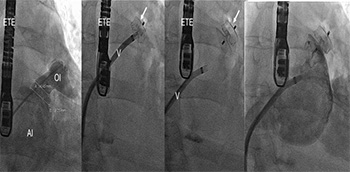

El cierre percutáneo de la orejuela izquierda ha surgido en los últimos años como una técnica capaz de evitar la necesidad de tratamiento anticoagulante en los pacientes con fibrilación auricular y alto riesgo embólico. Aunque los estudios aleatorizados sólo se han...